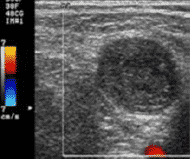

Detección de trombos y hematomas

La detección trombos y hematomas previos y posteriores a la canalización, evita realizar punciones sobre vasos ya dañados y optar por otros más adecuados y normo funcionantes.

En lo que a la técnica se refiere, también se utiliza la sonda lineal de alta frecuencia. En este caso es preferible el uso de Doppler a color, útil también para determinar permeabilidad, aunque también puede emplearse el modo 2D.

La ventaja de contar con Doppler a color es que este modo aporta información sobre la existencia y movimiento del flujo sanguíneo, siendo posible localizar regiones con flujo anormal. Queda representado de la siguiente forma:

En la detección de trombos se puede observar una imagen ecogénica heterogénea que ocupa total o parcialmente la luz venosa y se considera un signo prácticamente patognomónico la imposibilidad de comprimir la luz vascular por completo. Además, si utilizamos Doppler a color aplicado sobre la luz vascular se apreciará ausencia de flujo o algún defecto de repleción.

Los hematomas dan una imagen similar a la del trombo, pero se encontrarán ubicados por fuera del vaso, pudiendo llegar a comprimirlo o desplazarlo.